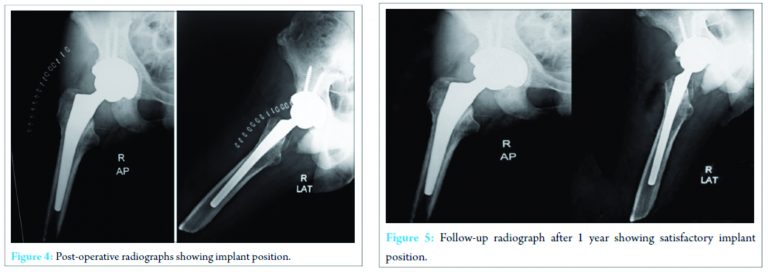

The patient tolerated the procedure well. The immediate postoperative period was uneventful. There was no infection, deep vein thrombosis, dislocation, or any other major complications. Postoperative radiographs showed proper placement of prosthesis (Fig. 4). He was allowed to be seated and perform isometric exercises after 48 hours of the procedure. He stayed in the hospital for 2 weeks till staple removal. During his hospitalization, he underwent supervised physiotherapy and was allowed full weight-bearing from postoperative day 2 with the help of previous exo-prosthesis and walking aid. He was followed up regularly till 12 months (Fig. 5). Harris hip score improved from preoperatively 36-80 at last follow-up. The patient continues to walk painlessly without any walking aid. X-ray at last follow-up shows well-incorporated femoral and acetabular components without any sign of osteolysis or subsidence.